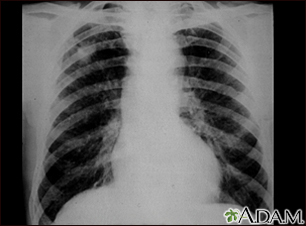

Coal workers pneumoconiosis - stage IIBackCoal workers pneumoconiosis - stage IIThis chest x-ray shows coal workers pneumoconiosis - stage II. There are diffuse, small (2 to 4 mm each), light areas throughout both lungs. In the right upper lung (seen on the left side of the picture), there is a light area (measuring approximately 2 cm by 4 cm) with poorly defined borders, representing coalescence (merging together) of previously distinct light areas. Diseases which may explain these x-ray findings include simple coal workers pneumoconiosis (CWP) - stage II, silico-tuberculosis, disseminated tuberculosis, metastatic lung cancer, and other diffuse infiltrative pulmonary diseases. E-mail FormEmail ResultsName:Email address:Recipients Name:Recipients address:Message: